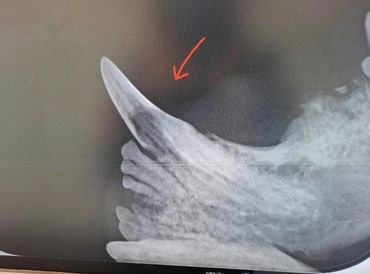

Syöpymä alkaa hammassementistä ja usein hampaan kaula-alueelta, aiheuttaa hampaan juurialueella normaalin rakenteen häviämisen. Edetessään sairaus aiheuttaa hampaan juuren sulautumisen leukaluuhun. Hampaan ydin säilyy elävänä kuitenkin hyvin pitkään. Vähitellen muutokset etenevät juurialueelta kruunun dentiiniin ja sitten hampaan kiilteeseen. Pikkuhiljaa kiille murtuu tai resorpoituu ja aiheuttaa siten kipua syöpymän puhjetessa suuontelon puolella. Vauriot tulevat tyypillisimmin alapremolareissa ja kulmahampaissa.

Hammassresorptioita on eri tyyppejä. Toisessa muodossa hammasjuuri sulautuu leukaluuhun (korvautuva, tyyppi 2) ja toisessa hampaaseen tulee tulehduskeskuksia (tulehduksellinen, tyyppi 1). Hampaassa voi esiintyä myös molempia tyyppejä (seka, tyyppi 3)

Ohessa röntgenkuva alakulmahampaasta, missä juurialueella jo pitkälle edennyt syöpymämuutos. Lisäksi havaitaan ensimmäisen premolarin kruunun irronneen syöpymämuutosten vuoksi.